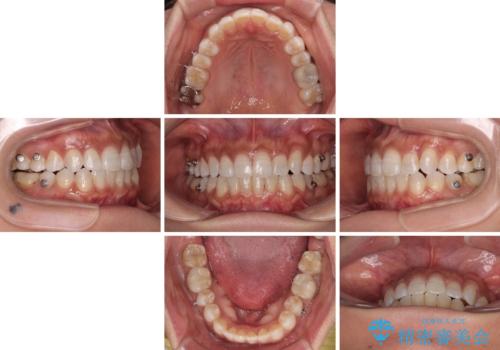

咬合力が非常に強く、治療が進むにつれて上下奥歯が離開してくることが予想されるため、治療途中から上下の顎間ゴムを使用することを理解いただき、インビザラインによる矯正治療を行うこととしました。

咬合力による臼歯離開は顎間ゴムで改善されましたが、それとは別に下顎小臼歯がマウスピースに追従せず、補正のためのゴムかけが必要となりました。